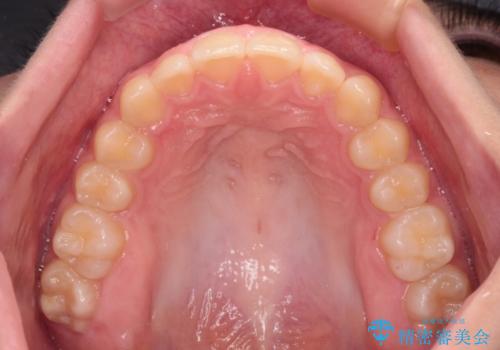

- ヨーロッパにてインビザライン矯正を始めたものの、日本に転居することになり、治療の継続を希望して来院された患者様です。

治療計画に無理がなく、現地担当医と速やかに連絡が取れるとのことで、インビザライン社での転医手続きを行い、継続して治療を行うこととしました。

舌の突出癖により、上下前歯が非接触となっていたため、トレーニングを徹底的に指導し、安定した咬み合わせにより終了させることができました。